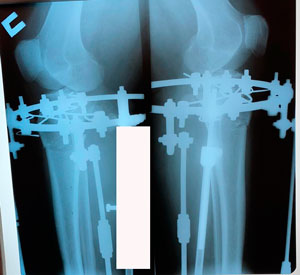

Исходник 39 лет.

Дата операции - 10.03.2020

на фиксации

Дата снятия аппаратов 29.07.2020

3 месяца с момента снятия аппаратов